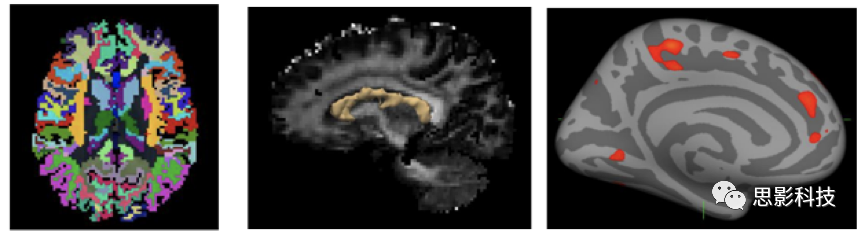

三、基于表面的形態(tài)學測量分析(SBM

基于表面的皮層指標計算,也可以精確地實現(xiàn)。

1.組織分割與皮層重建。對結構像進行分割,并重建皮層。

2.皮層指標計算。主要有:

1) 常規(guī)皮層指標,包括皮層厚度、曲率等;

2)復雜度指標,包括局部回指數(shù)、腦溝深度、分形維度等指標。

圖示.組織分割、皮層重建、皮層指標。